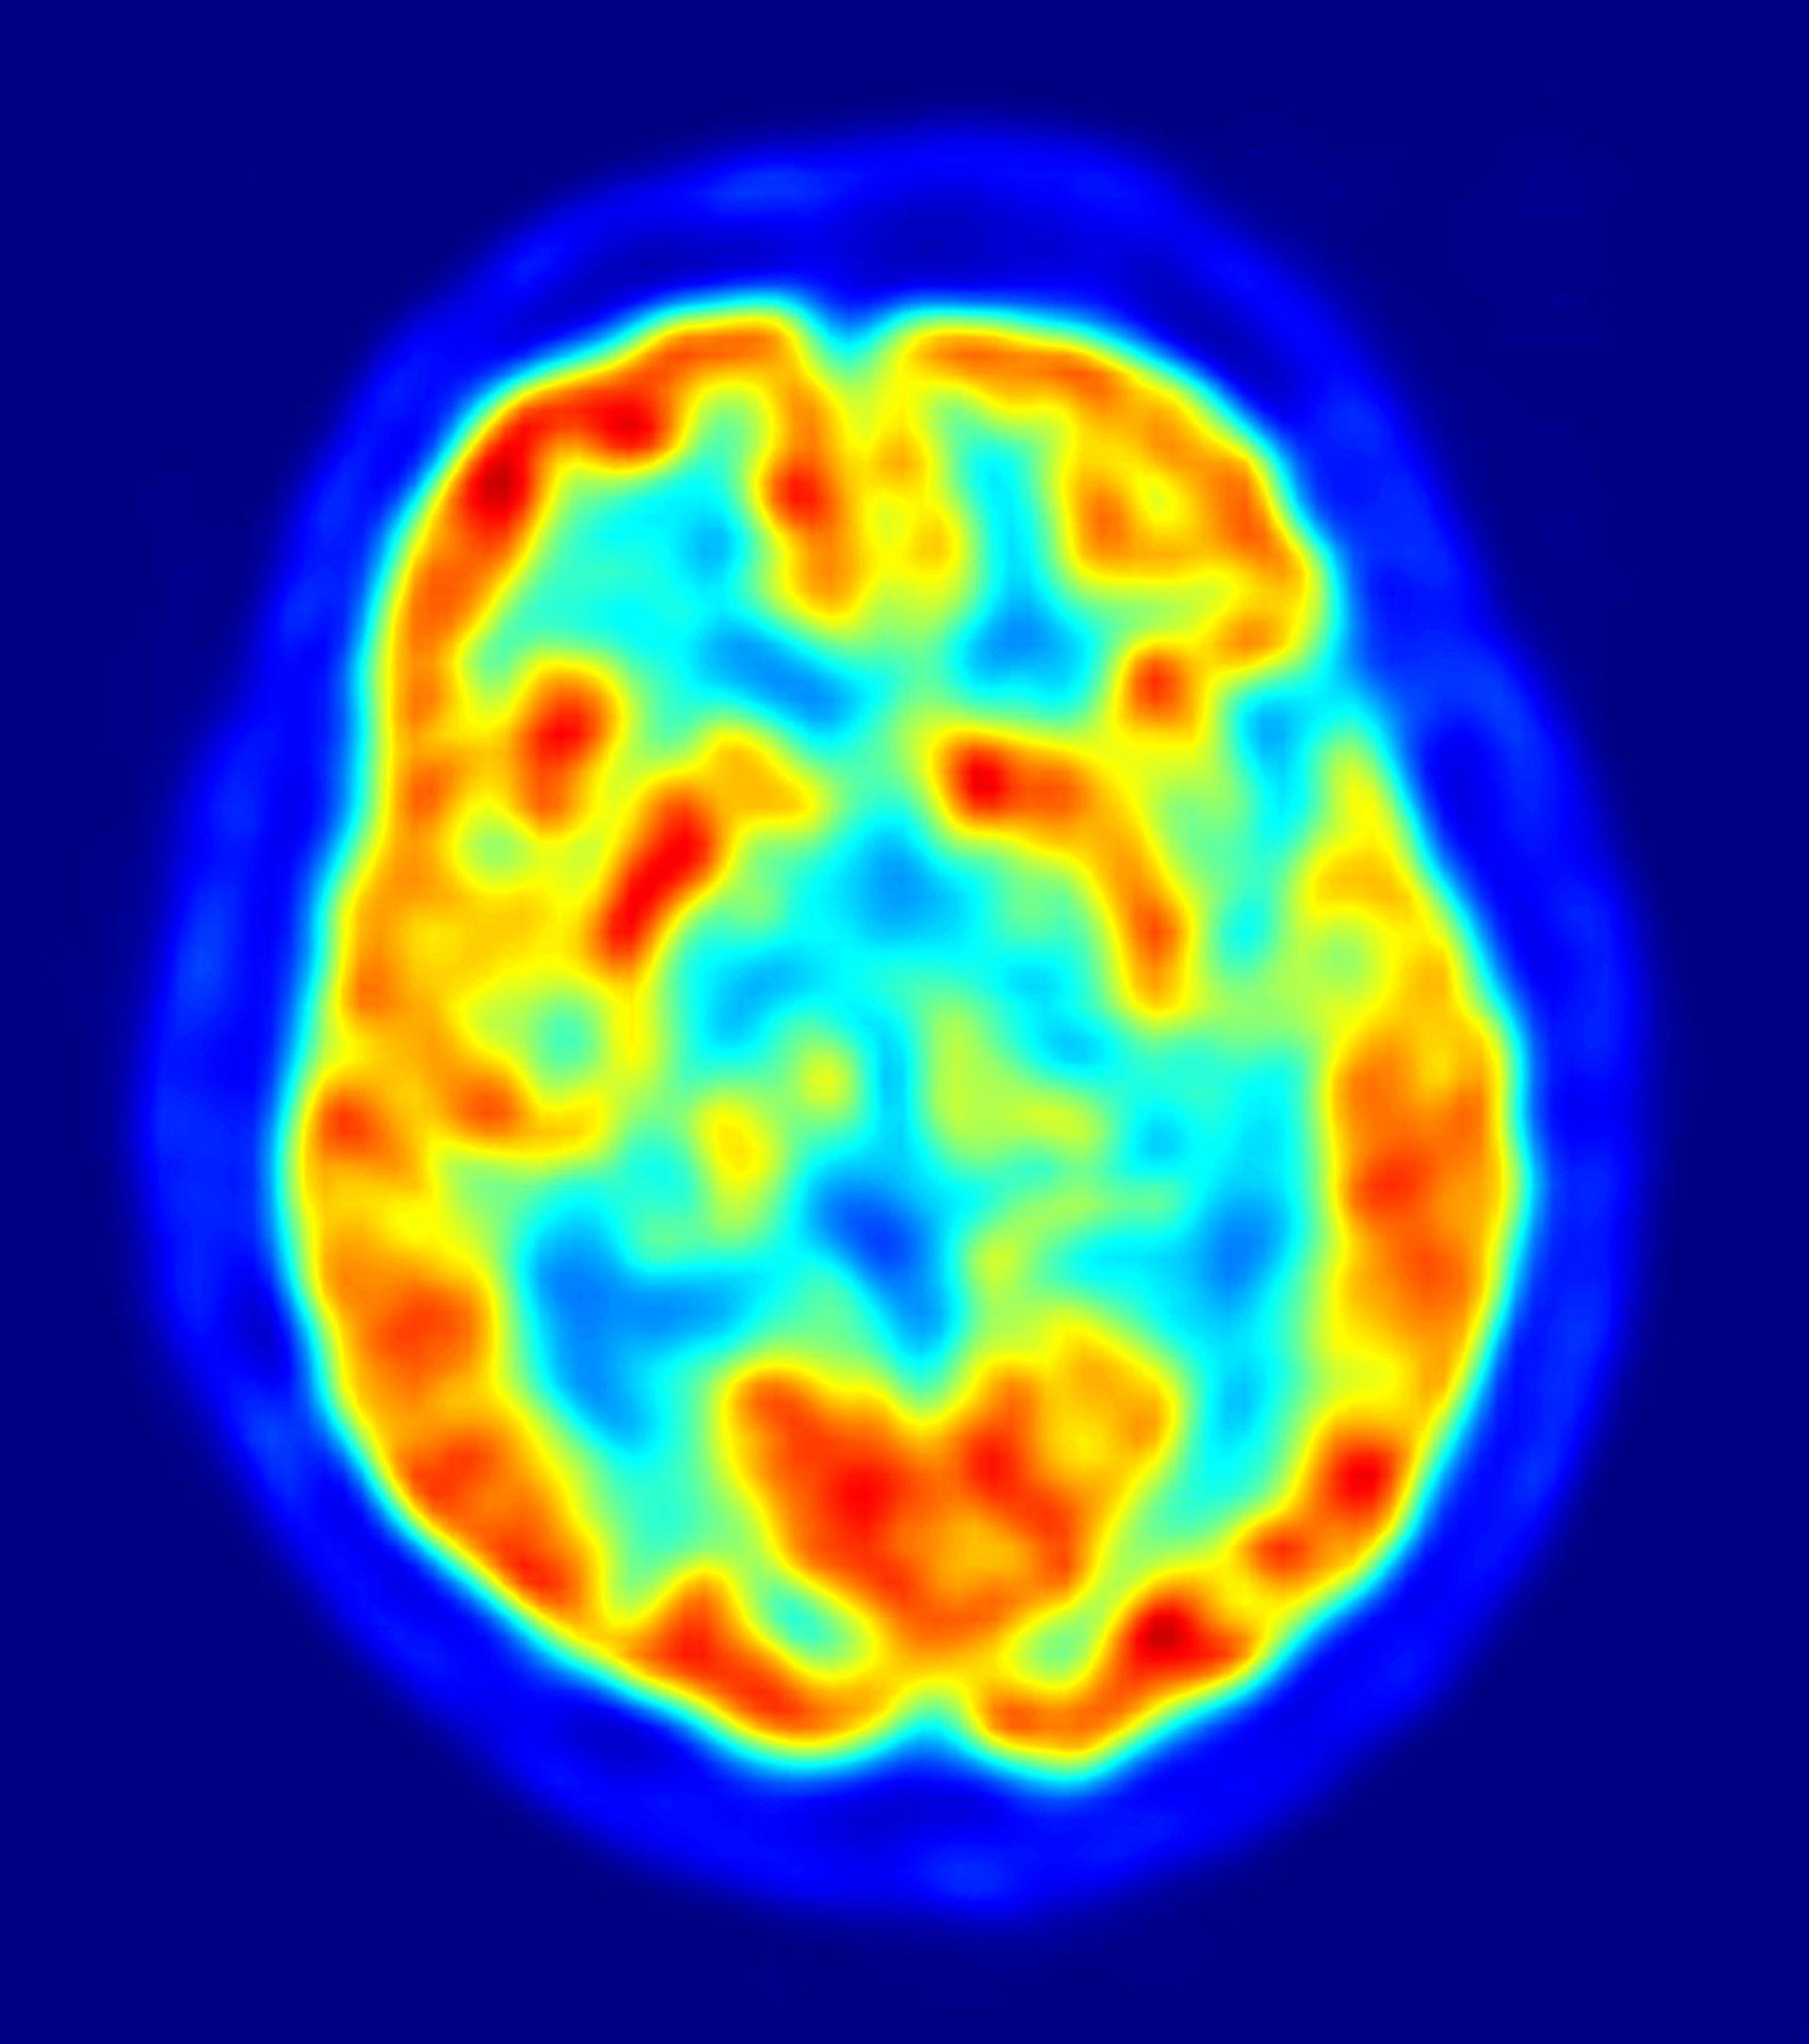

Un equipo investigador del grupo de Neuropsicología Clínica del Instituto Universitario de Investigación en Ciencias de la Salud (UNICS) de la Universidad de Baleares ha realizado un valioso hallazgo al descubrir que la parte prefrontal del cerebro humano funciona como la red de Internet, pudiendo realizar múltiples y nuevas conexiones neuronales en el caso de que una lesión dañara esa región del cerebro.

El doctor Francisco Barceló, responsable del equipo científico del UNICS, ha liderado la investigación, llevada a cabo de forma conjunta con la Universidad de California (EE.UU.), y que ahora recoge la revista 'Neuron'. Así, el estudio concluye que esa parte del cerebro humano funciona "en red", lo que significa que si a consecuencia de una lesión física esa región sufre daños irreparables los circuitos neuronales se "reconfiguran en cuestión de segundos", estableciendo nuevas conexiones y permitiendo que fluya la información de nuevo.

"Ello no conlleva la reparación del daño, sino que éste se ve compensado gracias a la gran plasticidad de esa parte del cerebro, en la que se encuentra una red flexible y dinámica de interconexiones neuronales", ha explicado el doctor Barceló en declaraciones a Europa Press.

Así, el investigador destaca que la importancia del descubrimiento reside en que durante décadas la parte prefrontal del cerebro fue un "misterio" y se la llegó a considerar "silente". "La comunidad científica llegó a pensar que no tenía ninguna función, debido a que muchos pacientes que habían sufrido lesiones en el córtex prefrontal mostraban una recuperación asombrosa de sus facultades, como si no hubieran sufrido ningún daño", ha relatado.

La explicación, aclara Barceló, se encuentra en la gran "plasticidad neuronal" de esa parte del cerebro, lo que permite superar lesiones gracias a la "continua reconfiguración" de las conexiones neuronales.

La región prefrontal controla la parte más "intrínsecamente humana" del cerebro, relacionada con "la capacidad de comprender el lenguaje hablado, de recordar el pasado o sentir y emocionarnos con esos recuerdos. Afecta a la capacidad de planificar el futuro, o ser animales sociales", detalla el investigador de la UIB.

Así, los investigadores han establecido una comparación entre el cerebro y la red y han concluido que las neuronas se comportan como si navegaran por Internet, quedando probada la gran capacidad para "readaptarse" al nuevo entorno tras una lesión. "La existencia de Internet nos ha ayudado mucho a entender nuestro cerebro", ha concluye el doctor Barceló.